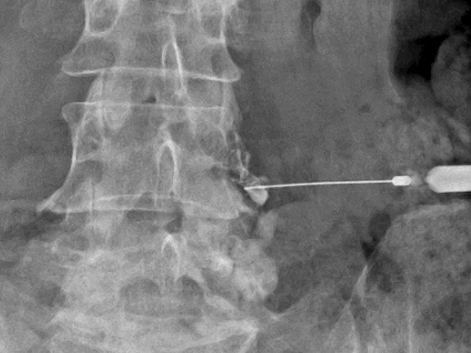

신경차단술이란 척추의 중심 신경에서 빠져나와 허리 통증을 유발하는 신경 가지를 찾아, 주사로 약물을 주입해 치료하는 방법입니다.

척추 내에 주사하는 기존 방법과 달리, 영상정밀장치(C-ARM)를 이용해 머리카락처럼 가는 신경부위를 하나씩 찾아내 치료하므로 안전하고 치료 효과가 뛰어납니다. 선택적 신경차단술은 척추의 중심신경에서 빠져 나온 여러가지 신경뿌리 중 통증을 일으키는 신경뿌리를 정확히 찾아 주사로 약물을 주입하여 통증을 완화시킵니다.

• 03 척추마취에 사용하는 주사침을 삽입해 원하는 위치에 도달시킵니다.

• 04 조영제를 투여하여 약이 퍼질 위치를 확인한 후 준비된 약제를 투여합니다.